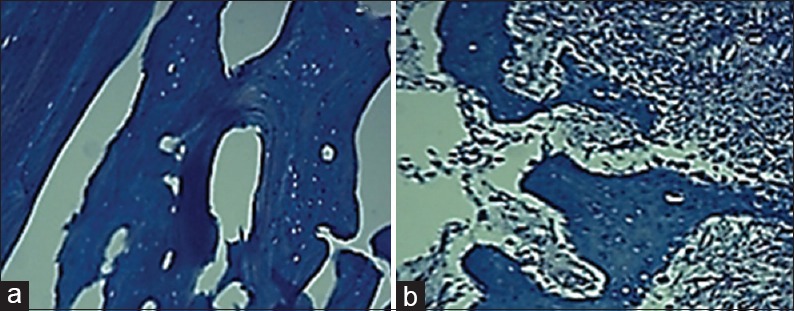

Evaluation of tissue sections revealed the formation of bone trabeculae and lacunae. This histological evaluation showed that the bone trabecular and the mineral matrices were thicker in the test group rather than the cell-free group [Figures 5 and 6].

Figure 5.

Formation of bone tissue with trabeculae in bone defects. (a) Cell-free group, (b) test group (H and E, ×100)

Figure 6.

Trichrome mallory staining indicated the existence of Type I collagen in bone matrix in both groups. (a) Cell-free group (b) test group (×100)